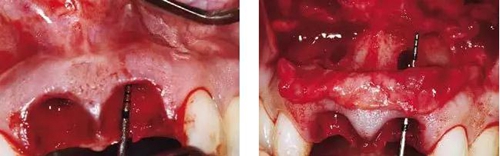

圖7、去除了肉芽組織和根尖感染組織,仔細(xì)沖洗后,可見雙側(cè)拔牙窩唇側(cè)骨壁有大面積缺損。

圖8、植入2顆Camlog平行壁螺紋種植體,扭矩達(dá)35Ncm。安放兩個(gè)粗直徑的愈合帽,防止軟組織退縮和凹陷。

圖9、頰側(cè)骨壁用自體骨覆蓋,Geistlich Bio-Oss®覆蓋在自體骨的外側(cè),Geistlich Bio-Oss®同樣也要放置在基臺(tái)與牙齦之間,以支撐牙齦的外形。

圖10、為了避免對植骨區(qū)的干擾,外側(cè)覆蓋Geistlich Bio-Gide®膠原膜。